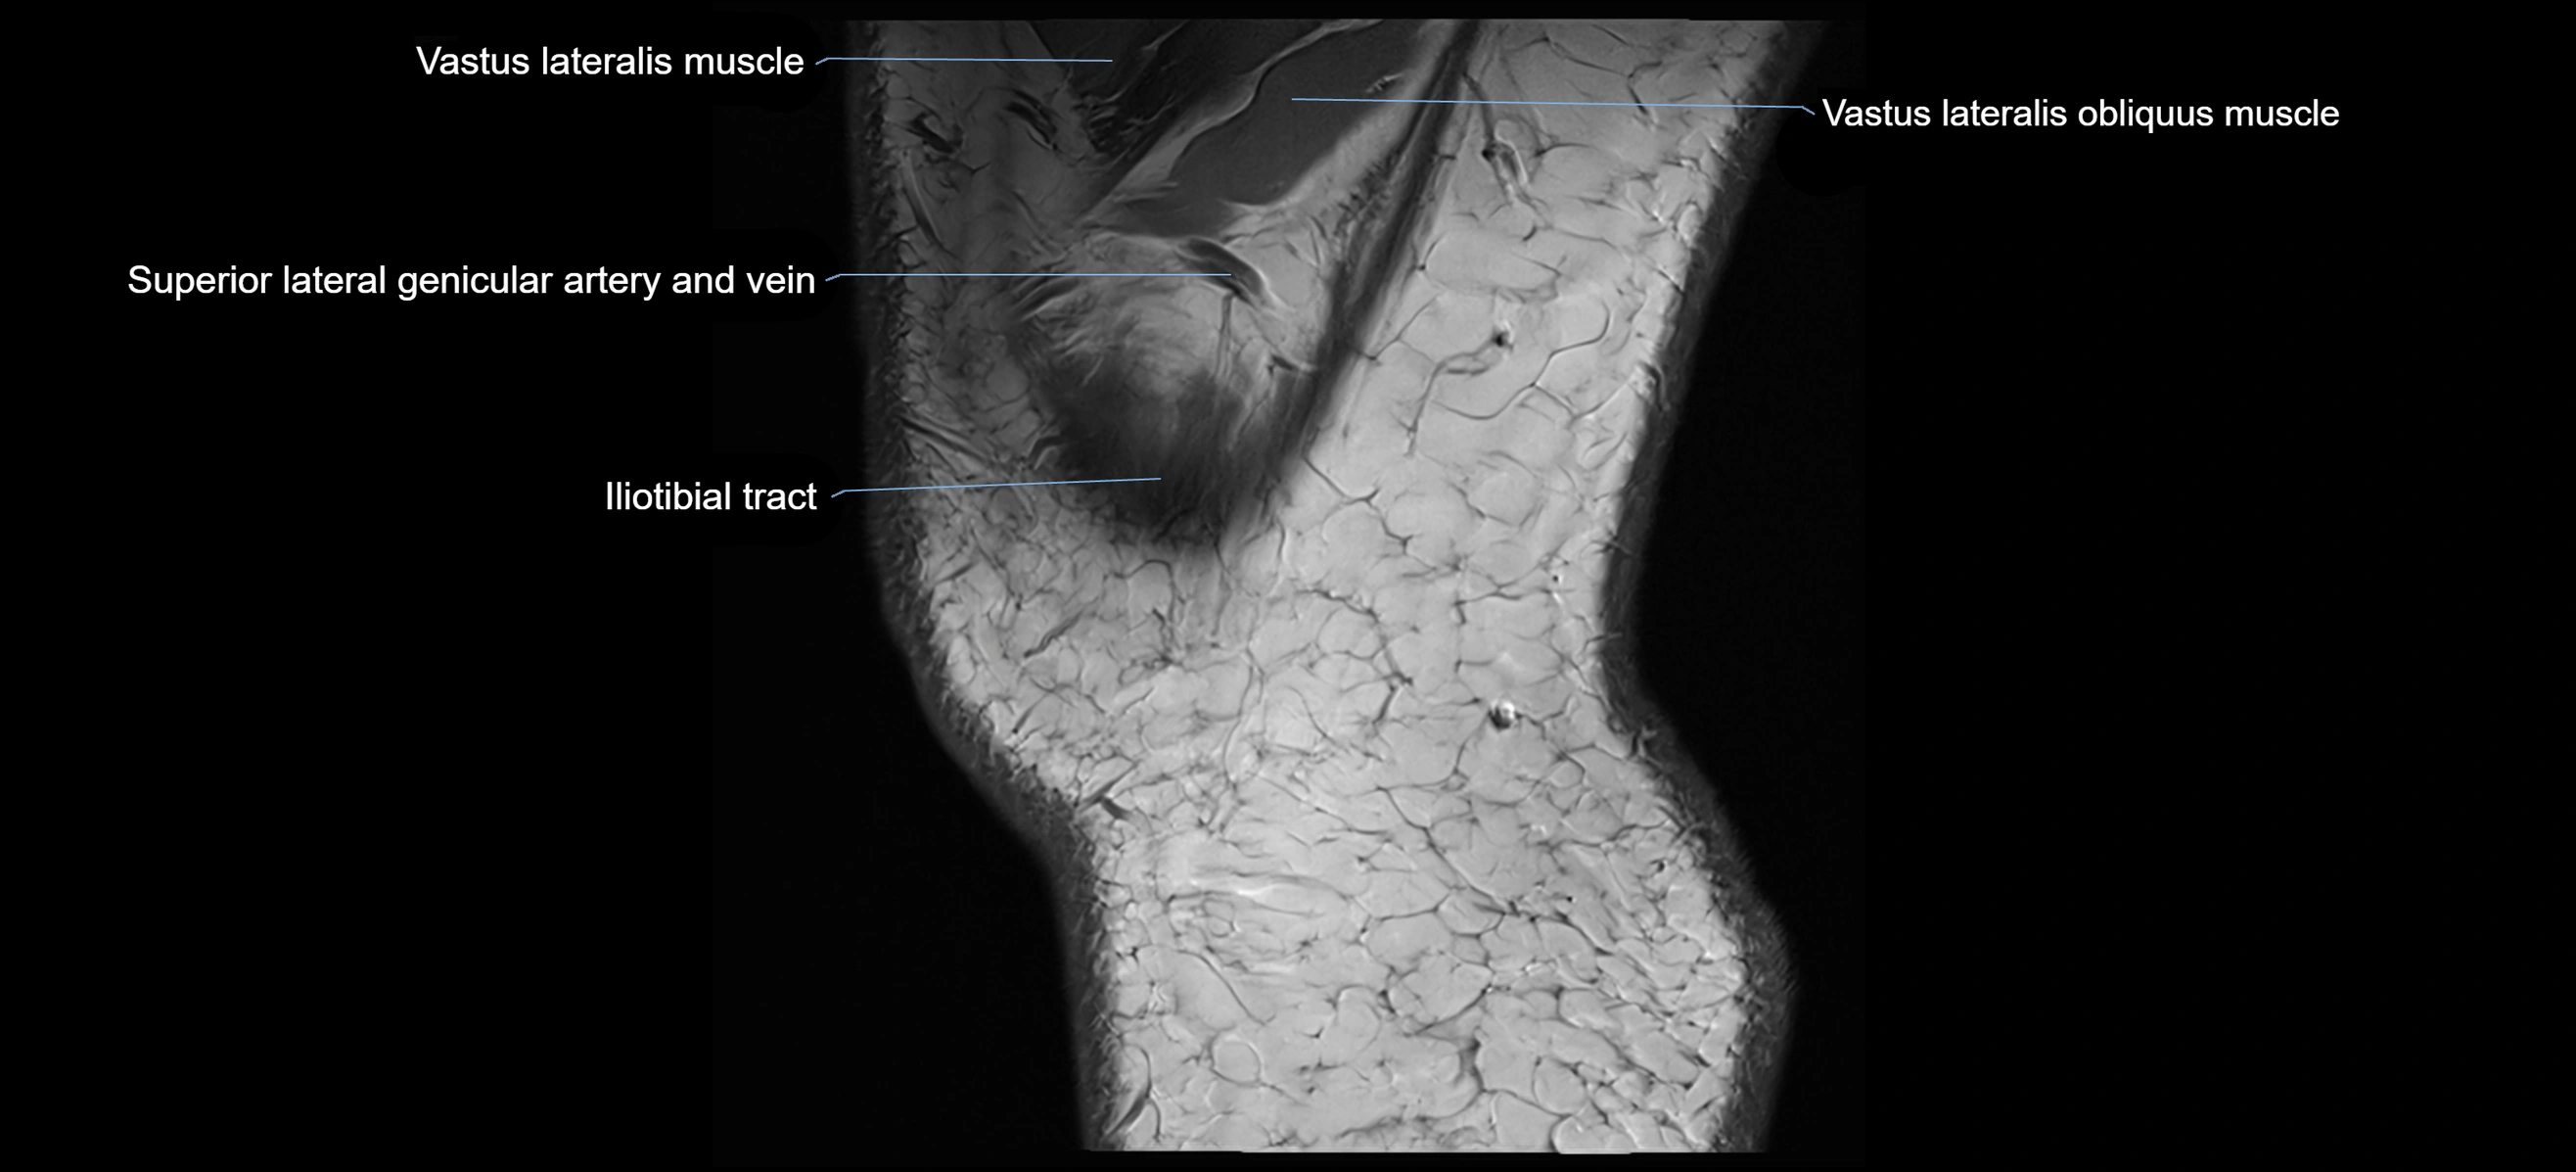

- Tensor fasciae latae muscle

- Vastus Lateralis Obliquus Muscle

- Vastus lateralis muscle

- Superior lateral genicular artery

- Superior lateral genicular vein